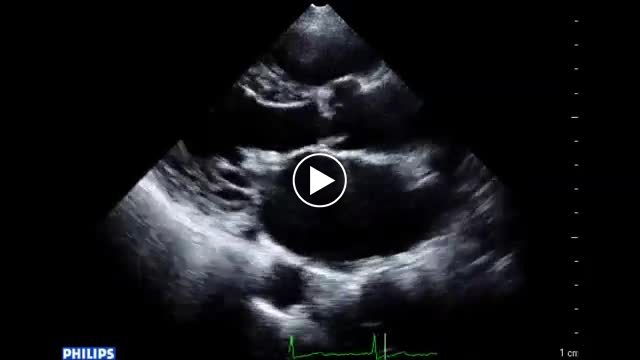

• 図4 心エコー図、手術所見 a

• 図5 心エコー、手術所見 a